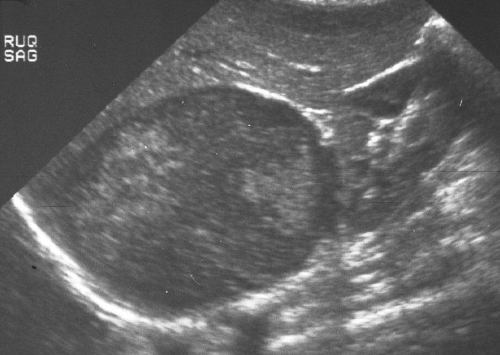

Ultrasound is quick, and a relatively inexpensive technology, but it has significant limitations in adrenal scanning. The adrenal glands are difficult to examine by ultrasound because of their small size, their location high in the abdomen under the rib cage, and the presence of retroperitoneal fat and bowel gas. In thin patients, the normal adrenal may be identified.An anterior or lateral approach may be necessary, particularly for the right adrenal gland, which occasionally can be seen through the liver. Bowel gas often impairs visualization of the left adrenal gland. A variety of patient positions and scanning windows are often required to adequately examine the glands.Since CT and MRI have so many diagnostic advantages, ultrasound is not used as the primary modality for the adrenal glands. Ultrasound can help in the characterization of large adrenal masses, as well as to define whether a suprarenal mass originates from the kidney or the adrenal. |

This image represents a solid mass that is half the size of the kidney below the mass. A mass of this size typically indicates a primary carcinoma, however, this case represents a large pheochromocytoma. Courtesy of: Ashley Davidoff, M.D. |